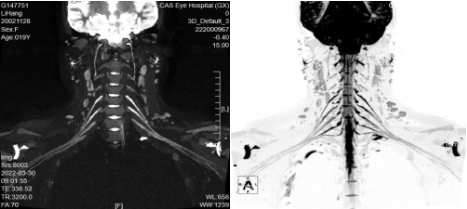

二、臂丛神经MRI成像(腰骶丛神经MRI成像)

上图是放射科开展的“臂丛神经MRI成像(腰骶丛神经MRI成像)”新业务,臂丛(腰骶丛)像一个复杂的地铁交通网,支配着上肢的感觉与运动。全球医学治疗难题之一就是臂丛神经损伤,它会导致患者上肢运动功能感觉的部分丧失或完全丧失,影响了患者的日常生活与工作。熟练掌握其分支、走形分布等可以为手术成功、减少术后并发症提供最有力的保障。当前对于臂丛及腰骶丛神经病变的诊断主要依靠临床症状、体征及电生理学检查等方法,但不能直观、准确观察神经损伤后形态学变化及周围结构的空间信息,对手术方案的选择及病情预后判断较为困难。MRI可以清晰显示臂丛及腰骶丛神经全貌及周围结构关系,为臂丛及腰骶丛神经创伤或肿瘤患者术前诊断及术后长期随访提供重要的信息,其在臂丛及腰骶丛神经诊断中有不可替代的作用。

MRI有以下优点:

(一)使正常神经显示为稍高信号,能清晰辨认神经内神经纤维束等结构;

(二)准确判断神经损伤部位和程度;

(三)准确评估病变是位于神经内还是神经外,这对判断肿瘤是否浸润脊髓以及选择治疗方案有重要意义。

适应症:外伤、肿瘤、炎症等疾病怀疑臂丛(腰骶)神经病变。

意义:能全程清晰显示臂丛(腰骶)神经,达到定性、定位的诊断,为精准治疗提供支持。

注意事项:需注入造影剂“钆喷酸葡胺”增强扫描。